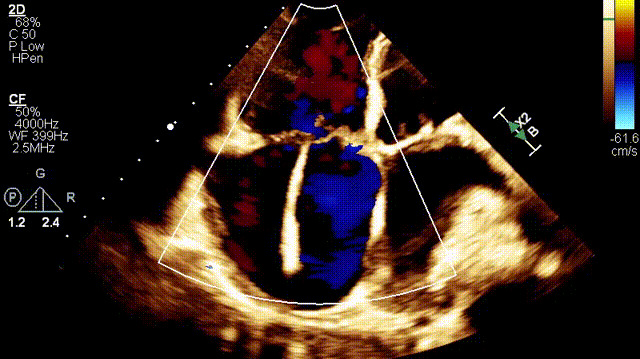

植入前超聲

接受治療的是一例89歲的超高齡女性患者,主訴“起搏器術(shù)后7年余,反復(fù)氣促4年”,因反復(fù)心衰失代償,胸腔積液就診。術(shù)前超聲提示:1.雙房及右室擴(kuò)大(右室舒張末和收縮末容積分別為55ml和21ml,右室FAC27%);2.三尖瓣瓣環(huán)擴(kuò)張(瓣環(huán)左右徑41mm,前葉長度21.3mm,隔葉長度15.2mm,后葉長度23.1mm),瓣葉閉合不攏;3.功能性重度三尖瓣反流(FTR 5+,收縮期三尖瓣口反流束縮流頸寬度21mm);4.下腔靜脈內(nèi)徑約25mm,呼吸塌陷率<50%;5.輕度肺高壓。術(shù)前CT結(jié)果顯示,入路血管最小平均徑約9.6mm,入路血管無嚴(yán)重迂曲、鈣化。隨后,王焱教授及其團(tuán)隊王斌教授、陳翔教授、超聲科蘇茂龍主任、手術(shù)室溫紅梅護(hù)士長進(jìn)行了詳細(xì)而周密的術(shù)前討論,最終選擇我國自主研發(fā)的LuX-Valve Plus經(jīng)血管三尖瓣置換系統(tǒng)對患者進(jìn)行手術(shù)。